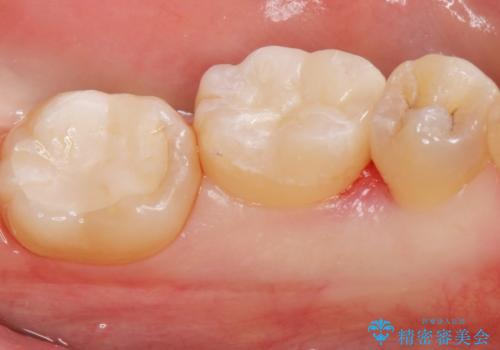

白い詰め物が入り患者様に満足して頂けました。

メタルインレーと比べてセラミックスのインレーは適合が良くて

虫歯の再発のリスクが少ないと言われています。